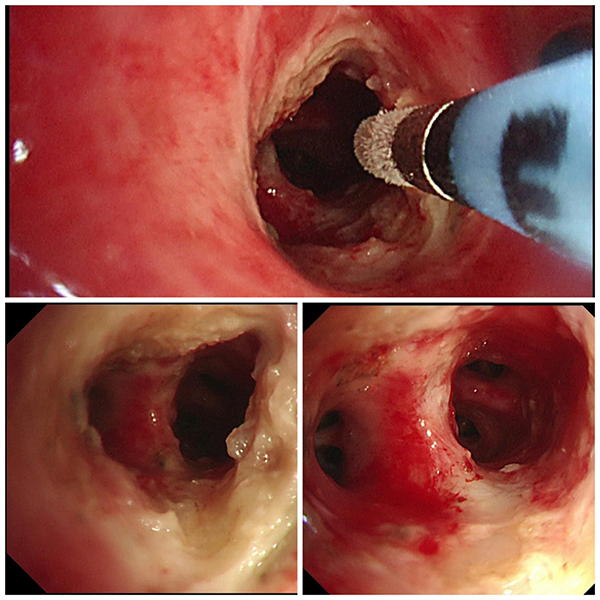

呼吸ICU團(tuán)隊(duì)李元芹副主任醫(yī)師、嵇桂娟副主任醫(yī)師及呼吸內(nèi)鏡團(tuán)隊(duì)孫理想主治醫(yī)師仔細(xì)閱讀胸部CT表現(xiàn),發(fā)現(xiàn)該患者右肺下葉體積縮小,出現(xiàn)阻塞性炎癥,支氣管粘液嵌塞,說明異物并非短期吸入。追問患者,患者近五年反復(fù)咳嗽,誤當(dāng)支氣管肺炎治療。為盡快明確異物阻塞位置和管腔內(nèi)情況,在入院當(dāng)天行RICU床旁氣管鏡探查。在嵇桂娟副主任醫(yī)師、李海俠主管護(hù)師的配合下,孫理想醫(yī)師小心翼翼地將支氣管鏡輸送到病人氣道,逐個(gè)葉段仔細(xì)探查,發(fā)現(xiàn)右肺下葉基地段開口見一膜狀物堵塞,氣道幾乎完全閉鎖,同時(shí)吸出大量血性分泌物。

RICU床邊支氣管鏡探明管腔阻塞情況后,陳碧主任主持病例討論下一步治療方案,李元芹副主任醫(yī)師、嵇桂娟副主任醫(yī)師等RICU團(tuán)隊(duì)及呼吸內(nèi)鏡團(tuán)隊(duì)劉平莉主任醫(yī)師、孫理想主治醫(yī)師仔細(xì)分析患者異物阻塞位置及管腔受累情況,制定了下一步呼吸內(nèi)鏡下治療方案:在呼吸內(nèi)鏡中心行全麻下氣管鏡腔內(nèi)肉芽組織清理+異物鉗取,先用高頻電刀放射狀切開,高頻電凝及鉗夾清除肉芽組織,觀察遠(yuǎn)端氣管情況,探查異物與周圍組織粘連情況。同時(shí)提出大出血預(yù)案,聯(lián)系胸外科張昊主任會(huì)診,做好了外科手術(shù)的緊急預(yù)案。

次日,在麻醉科的大力支持下,患者在呼吸內(nèi)鏡中心如期進(jìn)行內(nèi)鏡下手術(shù)。麻醉醫(yī)師為患者充分麻醉后,孫理想醫(yī)師按照術(shù)前規(guī)劃,先用高頻電刀放射狀切開,高頻電凝及鉗夾清除肉芽組織,吸除氣管分泌物,因遠(yuǎn)端氣道狹窄,異物與周圍組織粘連較為嚴(yán)重。通過耐心細(xì)致的逐層分離其表面肉芽,待異物完全暴露,確認(rèn)其與周邊不粘連,李海俠主管護(hù)師將異物緊緊鉗住,孫理想醫(yī)師通過不斷地調(diào)整內(nèi)鏡走向,盡可能地避免劃傷氣道黏膜。在醫(yī)護(hù)完美配合下,成功地將金屬異物取出,術(shù)中出血很少。

6月24日再次復(fù)查氣管鏡,清除患者右下葉基底段壞死物并行疤痕環(huán)形冷凍治療,術(shù)后無明顯出血,冷凍治療前后對比可見氣管狹窄明顯減輕。